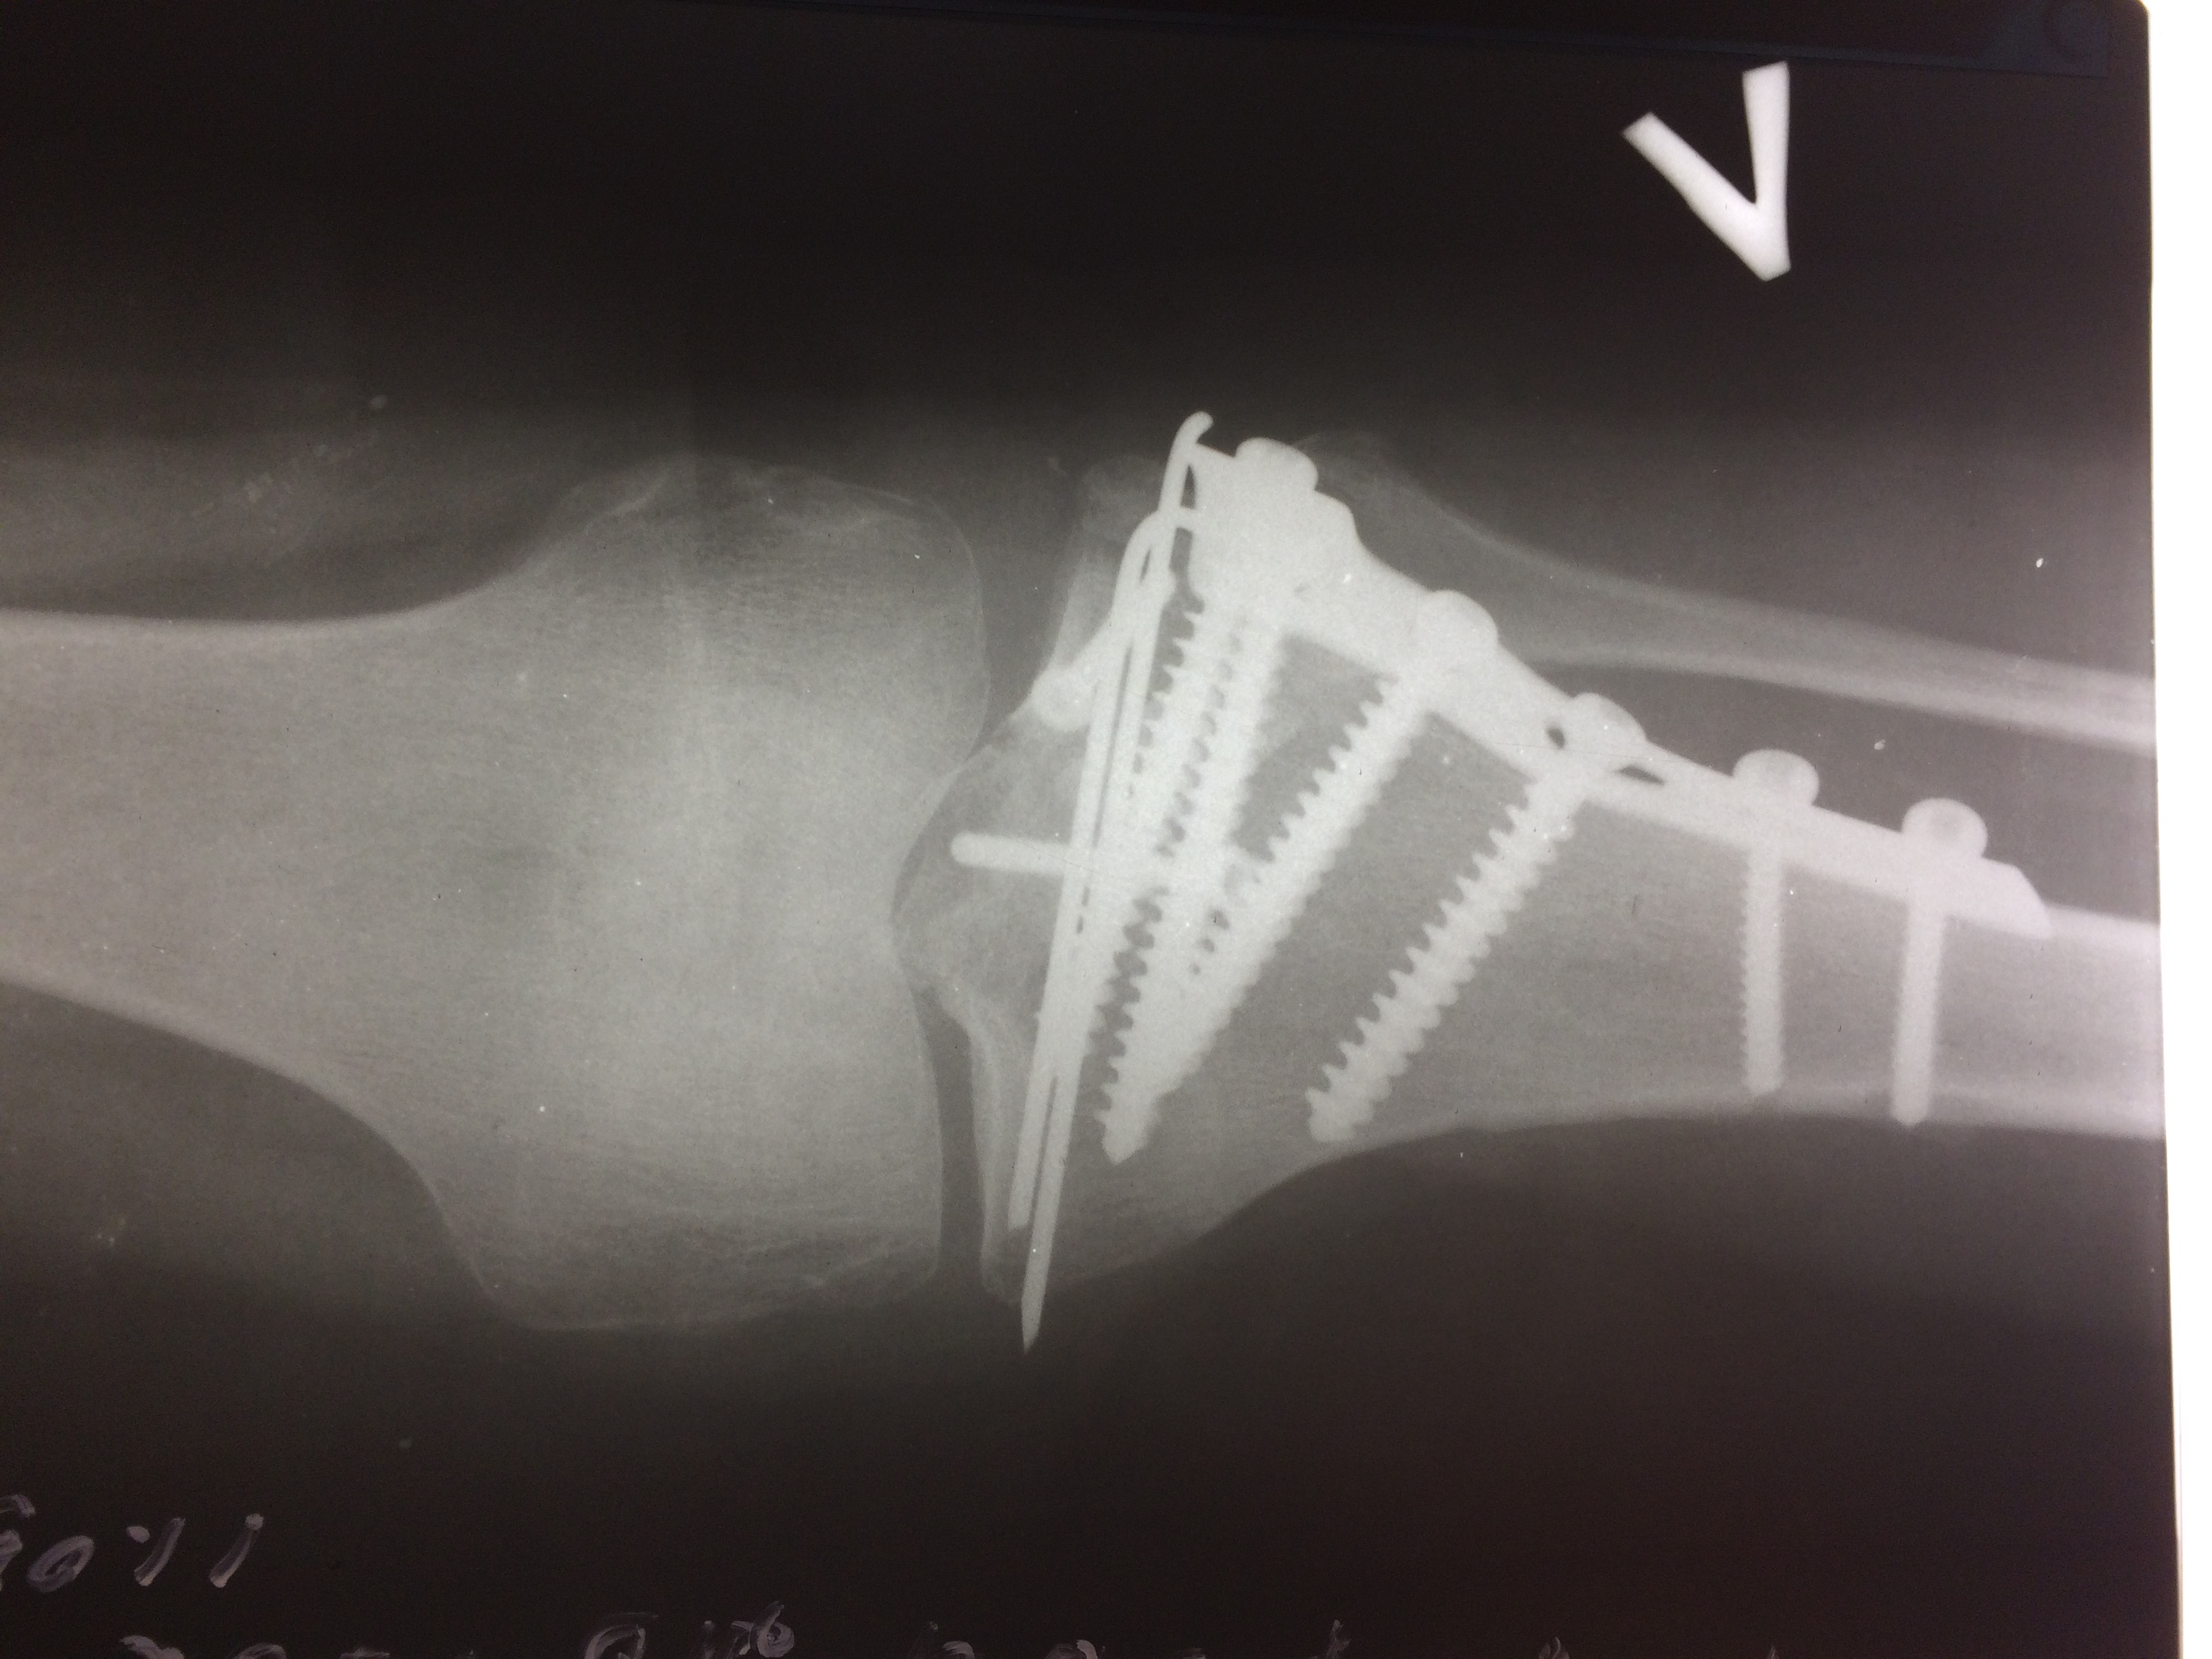

Операция - открытая репозиция, остеосинтез большеберцовой кости опорной пластиной с костной ксенопластикой маетриалом "Остеоматрикс". На контрольных снимках в три и шесть месяцев имеется консолидация перелома, миграции фиксатора нет, имеется остеоинтеграция ксенопластического материала. Функция коленного сустава полная.

Отдаленные результаты через 3 (три) месяца